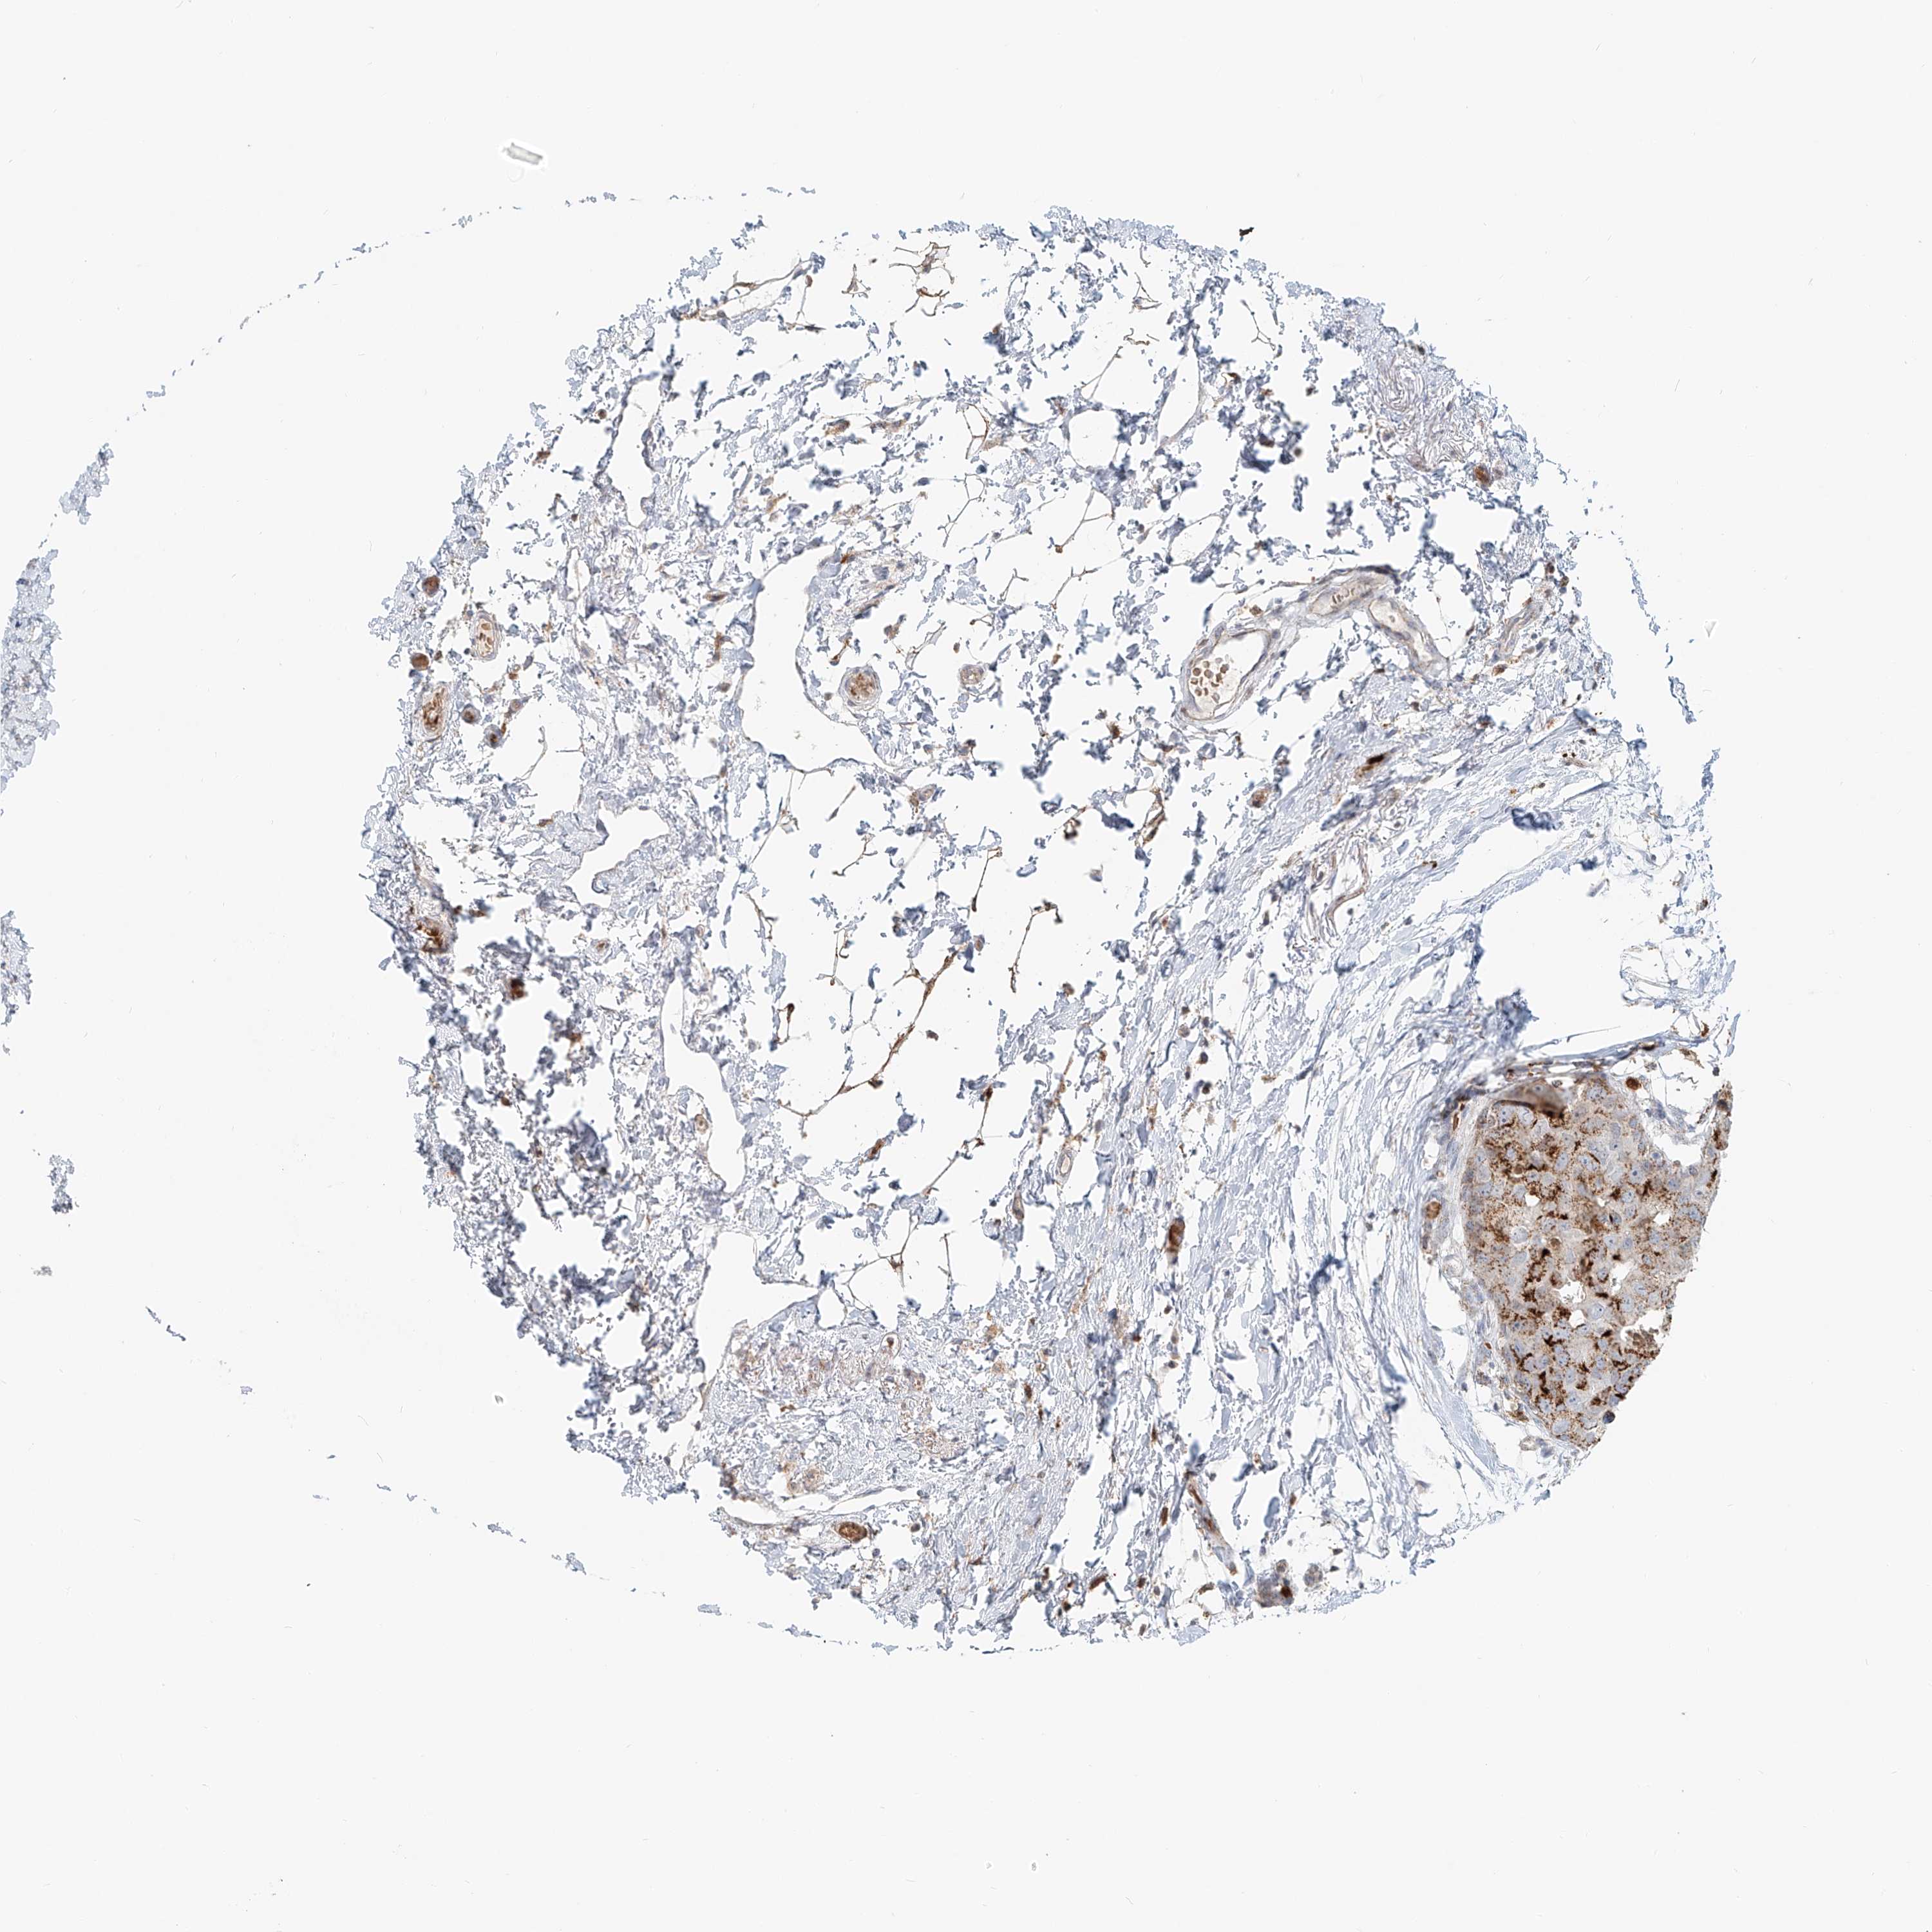

CANCER BREAST CANCER Show tissue menu

BRCA TCGA BRCA VALIDATION PROTEIN EXPRESSION